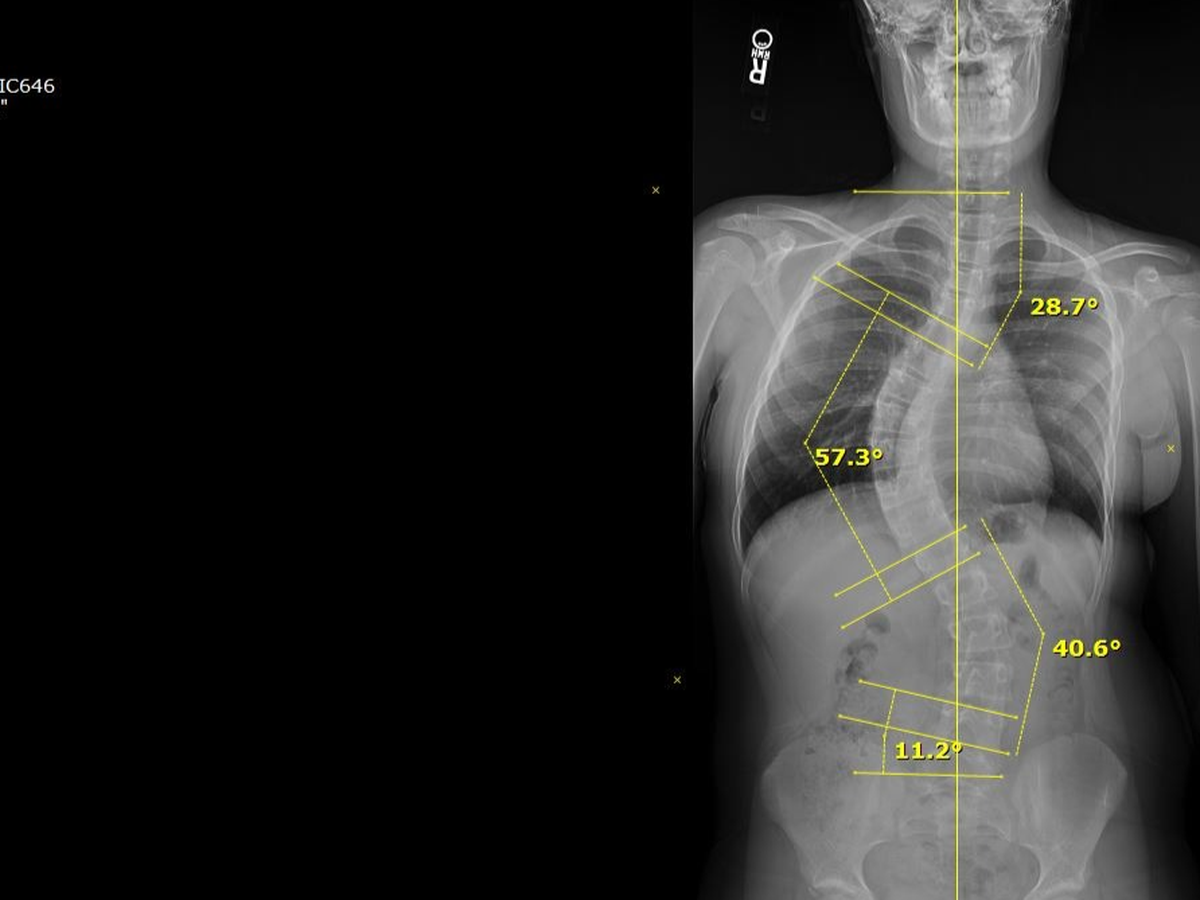

Her journey began just 2 months into her time on Earth with us. She was diagnosed with Cystic Fibrosis, and through her maintenance around that disease, we discovered the curvature in Azalya’s spine. At the time, we were told to just wait and see... little did we know, that is the last thing you want to do with a curve in your back while still growing. By the time she was seen again, her curve had significantly worsened, and we were referred to a specialist.

Last winter, we saw the specialist and were told there was nothing that could be done to reverse a scoliosis curve — and not to believe anyone who says otherwise. We were told she would need back surgery. We were determined to get a second opinion, and through some recommendations, we found the Scoliosis Care Center in San Jose.

After our initial inquiry and their team reviewing Azalya’s x-rays, things moved quickly. Due to the significance of her curvature and her age, we were urged to start treatments immediately. That meant school, dance, soccer, and Spring Break would have to wait. Two weeks later, we were in San Jose beginning our journey.